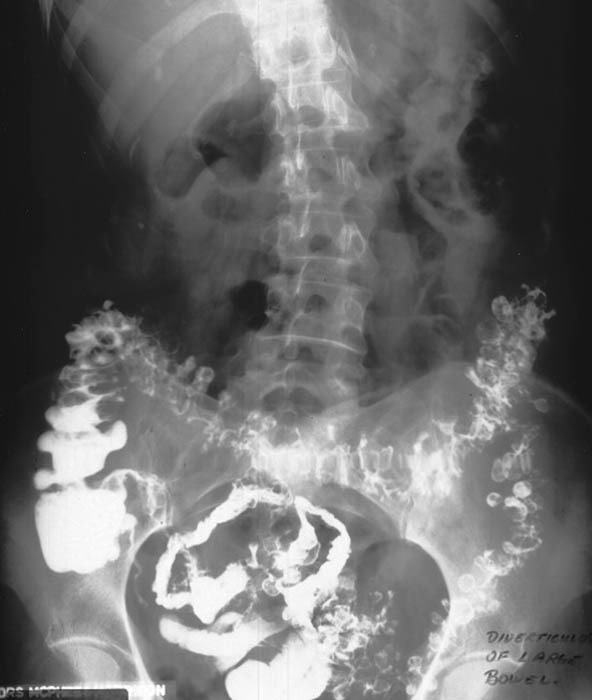

What are diverticula?

Outpouchings (herniations) of the mucosal layer through a weakened muscular layer of the bowel wall.

What is diverticulosis?

The presence of diverticula without inflammation.

What is diverticulitis?

The inflamed or infected form of diverticulosis, usually due to trapped fecal material.

Where do diverticula most commonly occur?

The sigmoid colon.